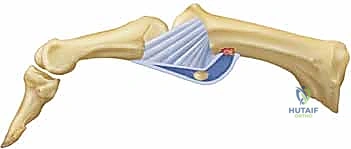

ما هي آفة ستينر (Stener Lesion)؟

تحدث هذه الحالة المعقدة عندما يتمزق الرباط الجانبي الزندي (UCL) بالكامل، وبدلاً من أن يبقى في مكانه ليلتئم، ينزلق الرباط الممزق ويصبح محاصراً فوق وتر عضلة أخرى (وتر العضلة المقربة للإبهام). هذا التداخل الميكانيكي يمنع التئام الرباط بشكل طبيعي تماماً، ويجعل التدخل الجراحي أمراً حتمياً لا مفر منه.